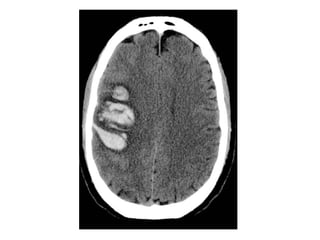

c) Hemorrhage :

-Frank hemorrhage into an arterial infarct

typically occurs a few days after the initial

stroke

-If there is hemorrhage within an infarct from

the outset , a venous stroke or arterial

embolus should be considered

-Hemorrhagic transformation with foci of hemorrhage

at the right post central gyrus

CT , Hemorrhagic evolution of initial ischemic infarction with

significant midline shift